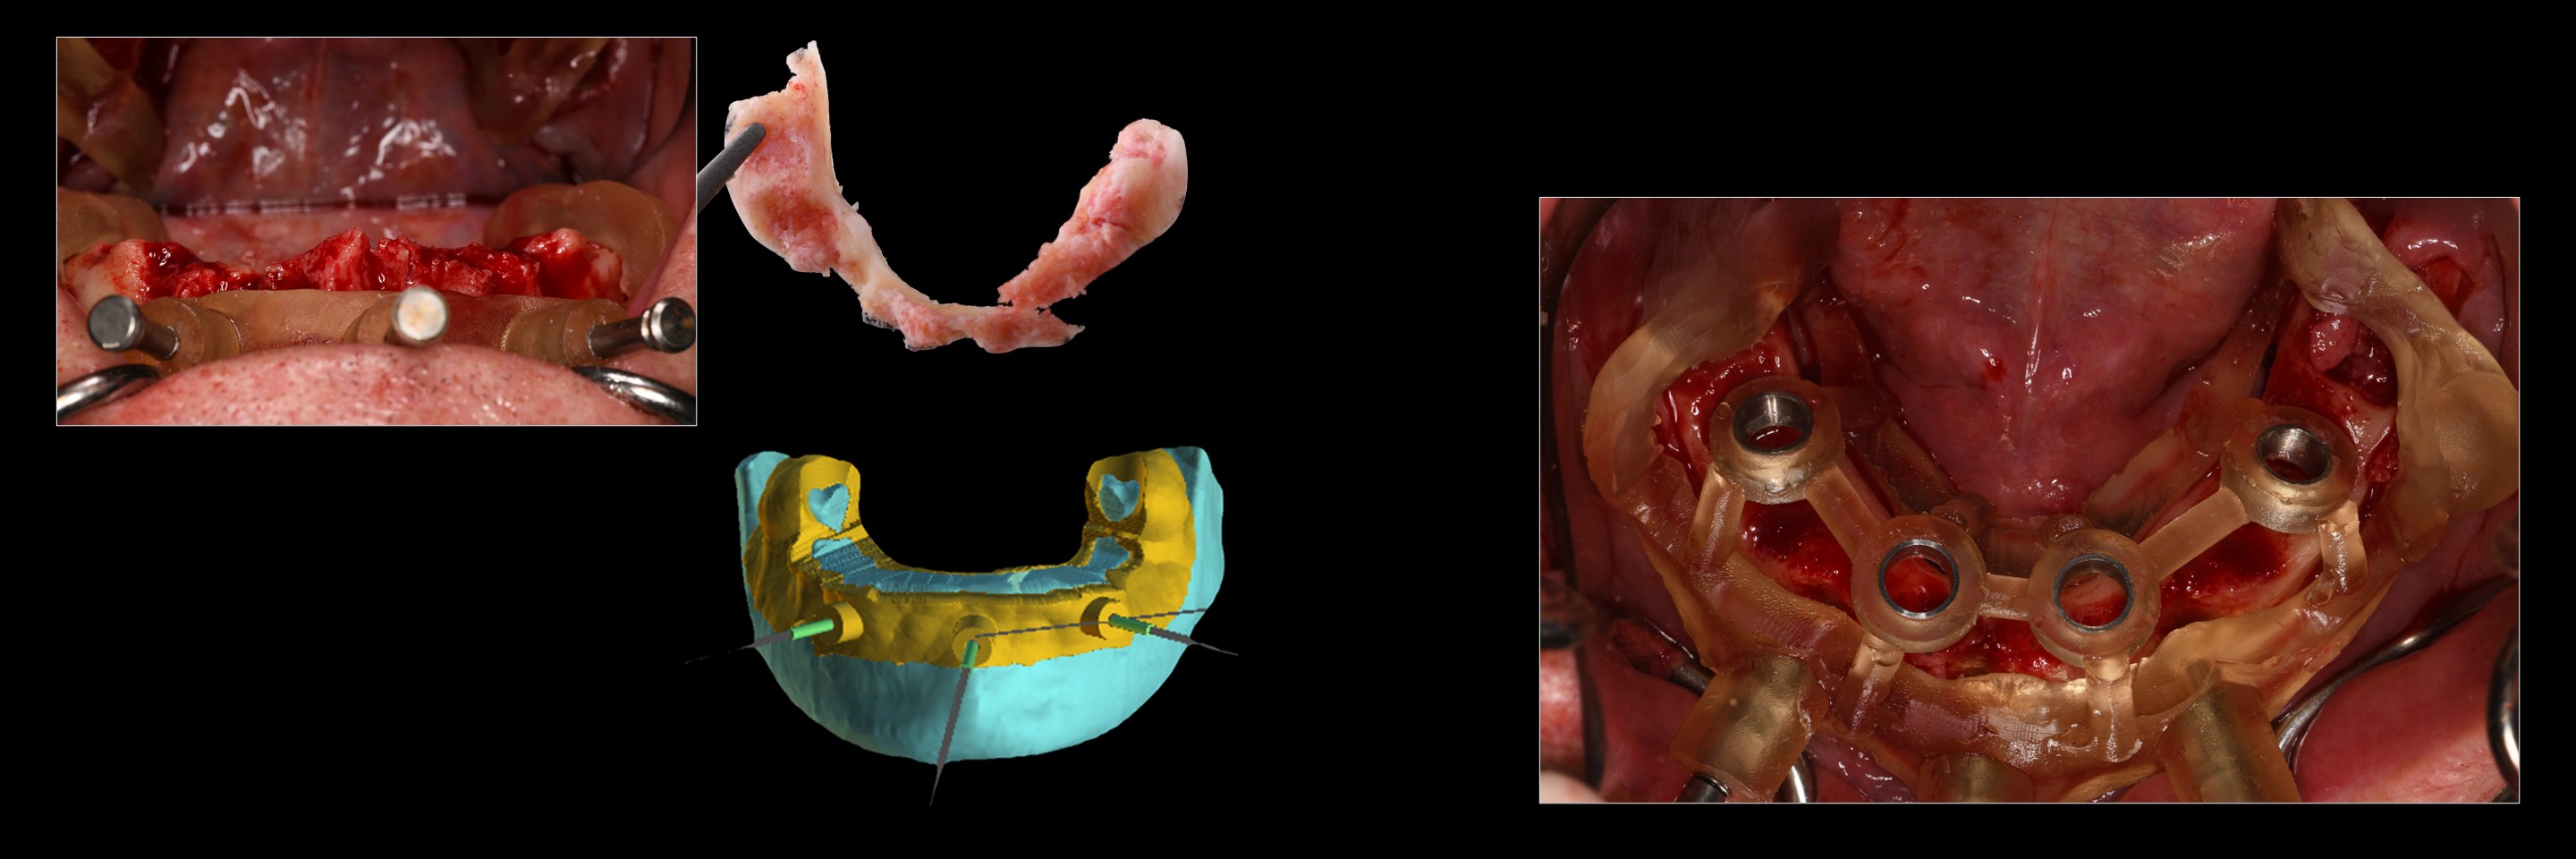

Director’s Clinical Cases

Director’s Clinical Cases